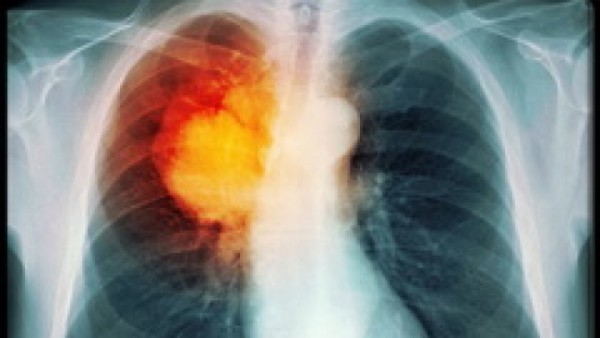

Ung thư phổi là căn bệnh nguy hiểm hàng đầu và bệnh ngày càng diễn ra phổ biến hiện nay. Vậy diễn biến ung thư phổi giai đoạn cuối như thế nào là câu hỏi của nhiều người. Ung thư phổi là bệnh lý ác tính bắt nguồn từ phổi. Bệnh tiến triển âm thầm, khó phát hiện sớm và tiên lượng khá dè dặt. Tuy nhiên ung thư phổi giai đoạn cuối lại có những dấu hiệu khá rõ ràng như: nuốt cảm giác rất khó khăn, đau đớn, khó thở, khàn giọng, ho ra máu, ho thường xuyên và liên tục hơn. Dưới đây chúng ta cùng đi tìm hiểu chi tiết diễn biến của ung thư phổi giai đoạn cuối như thế nào.

+ Ho ra máu: Ung thư phổi có thể gây chảy máu ở đường dẫn khí, khiến người bệnh bị ho ra máu. Đôi khi tình trạng chảy máu có thể trở nên nghiêm trọng và cần tới sự can thiệp của y tế.

+ Khó thở: Những người bị ung thư phổi có thể gặp tình trạng khó thở nếu bệnh ung thư phát triển đủ lớn để ngăn chặn các đường dẫn khí lớn. Ung thư phổi cũng có thể gây tích tụ chất lỏng xung quanh phổi, những chất dịch này lấp đầy khoang phổi, không còn không gian cho không khí, khiến người bệnh càng thêm khó thở.